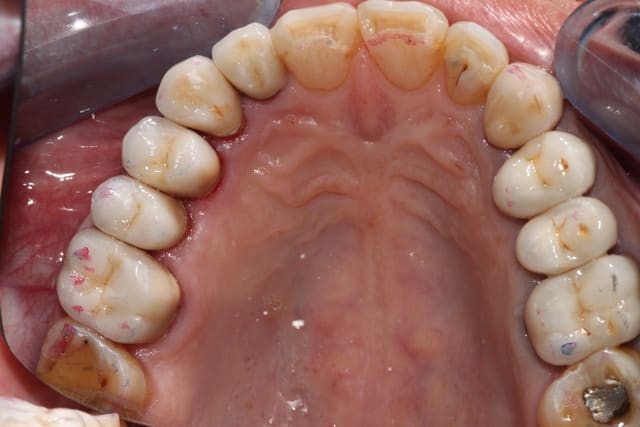

On relance, 2 compos tous frais, c'est basique mais ça me fait plaisir, en 35 minutes avec le détartrage on est presque au taux horaire, pas de stress...

Photos un peu floues, j'ai prêté mon miroir occlusal, désolé.

Img 2760 y33qry - Eugenol

Img 2759 ohq0n5 - Eugenol